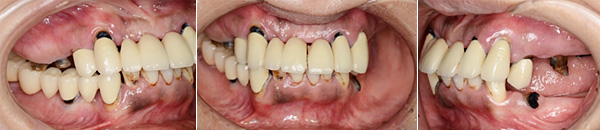

患者さんは40歳代の女性 重度の歯周病です。歯の本数が少なくなり噛み合わせを維持することができなくなる咬合崩壊がおこってます。そのために崩壊した噛み合わせを出来るだけ崩壊以前の元の状態にもどす咬合再構成が必要になります。フィスボウトランスファー(必要ないという先生もいますが、その人の咬み合わせを再現するときとても重要な診査です)をおこない、仮の適正な咬み合わせ(中止位)を咬合器(咬み合わせを再現させる装置)で再現し、理想的な咬み合わせのゴールを設定し(診断用ワックスアップ)、プロビジョナルレストレーション(治療用の仮歯)に置き換えていきます。それに合わせた位置にインプラントを入れていく必要があります。インプラント治療は目的でなく手段です。そして可能な限り天然歯(自分の歯)を残す歯周病の治療を行います。

初診時

フェイスボウトランスファーをおこない、中心位で咬合器につけました。咬合診断し、ポイントは咬み合わせの低下がみられたので、3㎜高くしました。